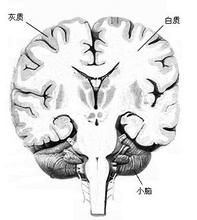

腦、脊髓內神經細胞體集中的地方,稱為灰質。灰質是一種神經組織,是中樞神經系統的重要組成部分。存在部位

在脊髓中,灰質存在於內部,白質包圍在灰質外面。大腦半球被覆灰質,稱大腦皮質,其深方為白質,稱為髓質。小腦灰質在外部,白質在內部。

3.大腦皮層灰質分布:大腦半球的表面(即大腦皮質)、小腦的表面(即小腦皮質)。大腦半球被灰質覆蓋,所以灰質稱大腦皮質,其深方為白質(whitematter),稱為髓質。